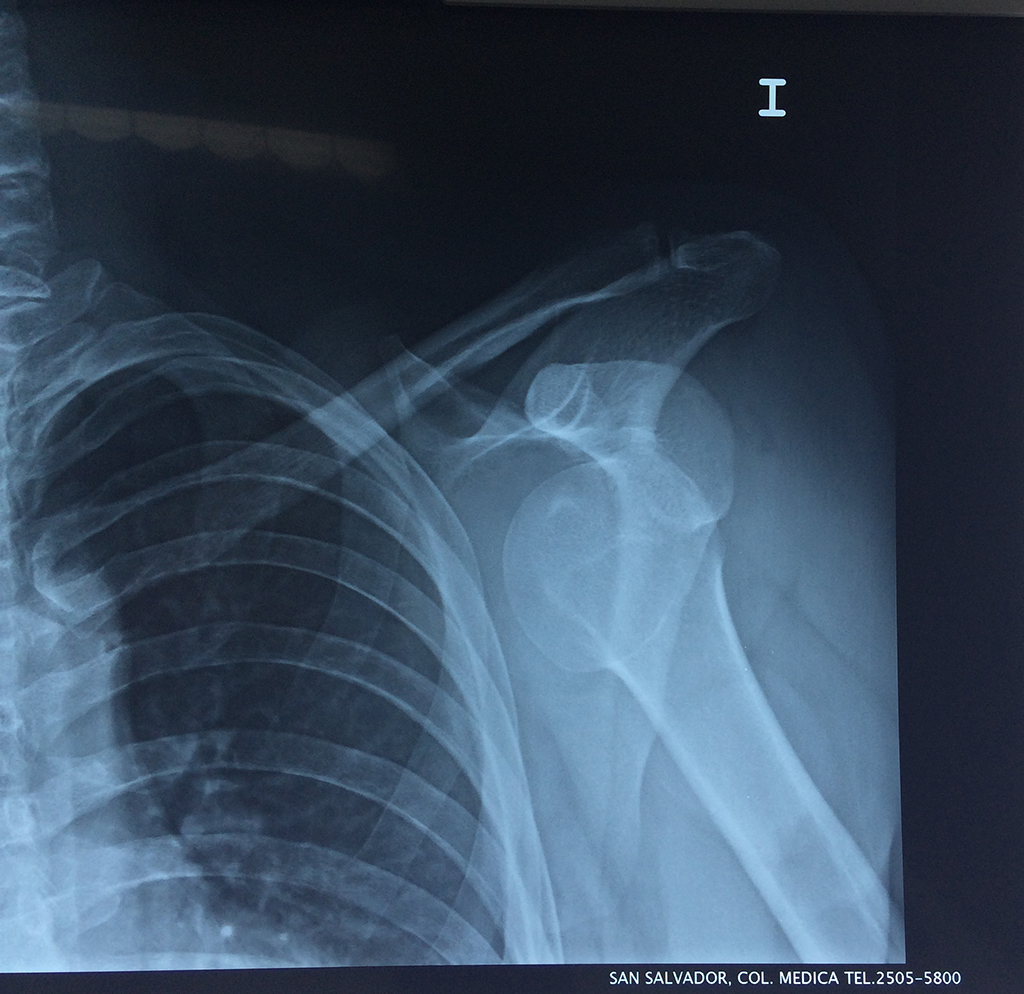

La principal articulación del hombro es la que une la cabeza del húmero con la escápula, recibe el nombre de articulación escapulohumeral y presenta dos superficies articulares, una de ellas corresponde a la cabeza del humero que tiene forma semiesférica y la otra es la cavidad glenoidea de la escápula, estas superficies están recubiertos por cartílago que permiten un movimiento suave e indoloro.

Exteriormente una envoltura de tejido blando circunda el conjunto, es la llamada cápsula articular que está reforzada por varios ligamentos que le dan estabilidad e impiden que los huesos se desplacen más allá de sus límites fisiológicos. Un conjunto de músculos y sus tendones se unen a las superficies de los huesos y hacen posible la movilidad de la articulación, entre ellos es muy importante el manguito rotador formado por cuatro músculos que proporcionan movilidad y estabilidad al hombro.